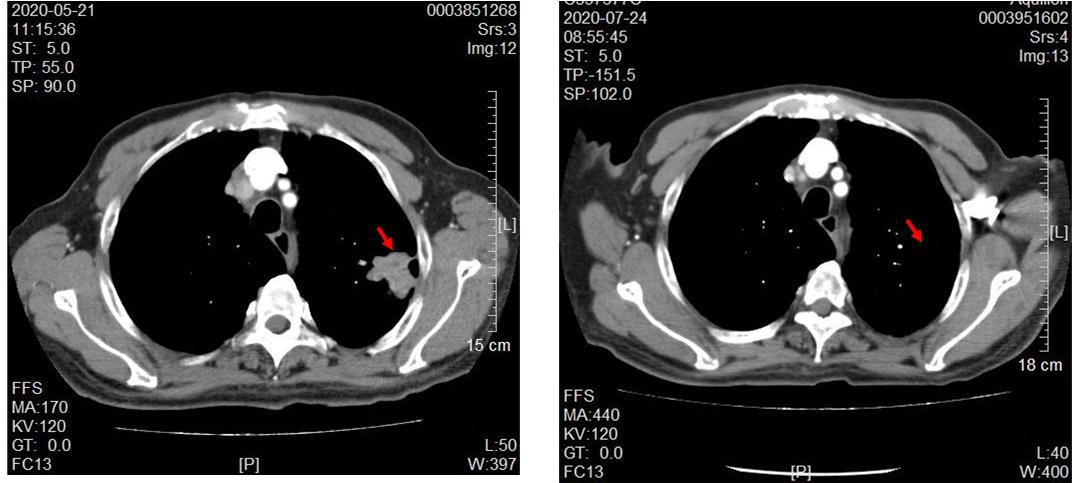

林老师在2月个半月因吞咽困难,进食固体食物时明显,半流质尚可,后进行性加重伴右侧颈部淋巴结肿大,淋巴结自行触摸有鸡蛋大小。电子胃镜:食管占位,病理提示是个鳞状细胞癌。螺旋CT直接增强(肺部):扫及食管中下段壁增厚,考虑恶性肿瘤;左肺上叶占位并周围少量阻塞性炎症,考虑肺癌;纵隔内、肝胃间隙及腹膜后多发肿大淋巴结。根据CT情况又做了左肺占位穿刺活检提示:"左肺穿刺活检组织"鳞状细胞癌。结合其影像学及病理学情况,考虑不排除肺、食管双源发肿瘤。经病例讨论后,给予了免疫+抗肿瘤血管生产靶向药+单药化疗药。1个周期后,林老师自觉吞咽困难情况明显改善,并且脖子上淋巴结渐渐摸不到了。2个周期后复查,肺部的肿块接近消失,食管肿块明显缩小。不得不感叹,肿瘤治疗的神奇之处。在传统观念里手术、放化疗常用*器武**,再加上现代新治疗方案靶向及免疫治疗,确实取得非常不错的效果。

肺部肿瘤接近消失

食管碧明显变薄